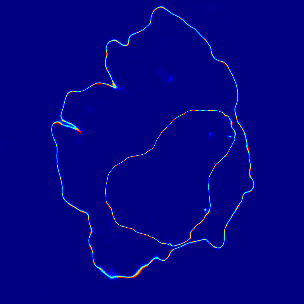

Figure 8: Attention map in Top-Down PDA-Module

4.3.4 Visualization of Top-Down PDA-Module

Visualization results of the attention map in Top-Down PDA Module are shown in Figure 8. In the first epoch, the probability of the correct class is low at almost pixels. In the second epoch, the probability of the correct class is low for the cell nucleus and red blood cells in the background. As training advances, we can see that the probability of the correct class is low at the edges and in small regions. This indicates that these pixels are more difficult to recognize than the other pixels. Since the pixels with relatively low probability for the correct class contain a lot of information for identifying the object’s outline, they are considered to be of relatively high importance during training.